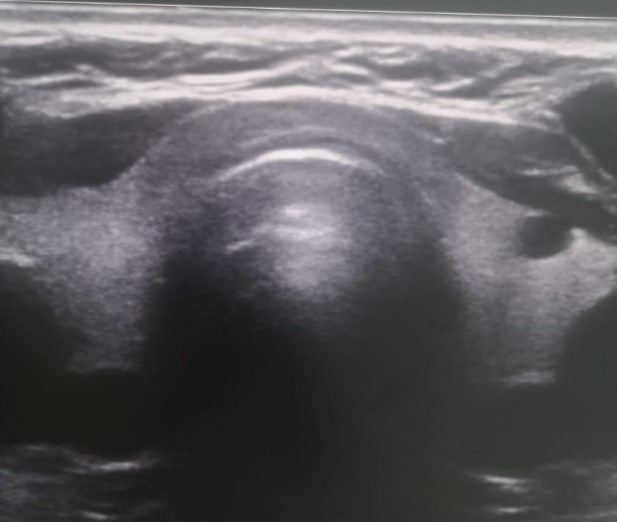

Ультразвуковое исследование (УЗИ) щитовидной железы (рисунок 2). Топография не изменена, структуры хорошо дифференцированы. Расположение типичное. Контуры ровные, чёткие. Капсула не уплотнена. Кровоснабжение правой доли 1 типа, левой доли 1 типа. Скорость по артериям щитовидной железы – 14,00 см/сек. Региональные лимфоузлы (паратрахеальные, яремные) не увеличены.

Рис. 2. УЗИ щитовидной железы. Патологических изменений не выявлено

Fig. 2. Ultrasound of the thyroid gland. No pathological changes were detected

Заключение. Тиреоидный объем – 14,68 см3. Патологических изменений щитовидной железы не выявлено.